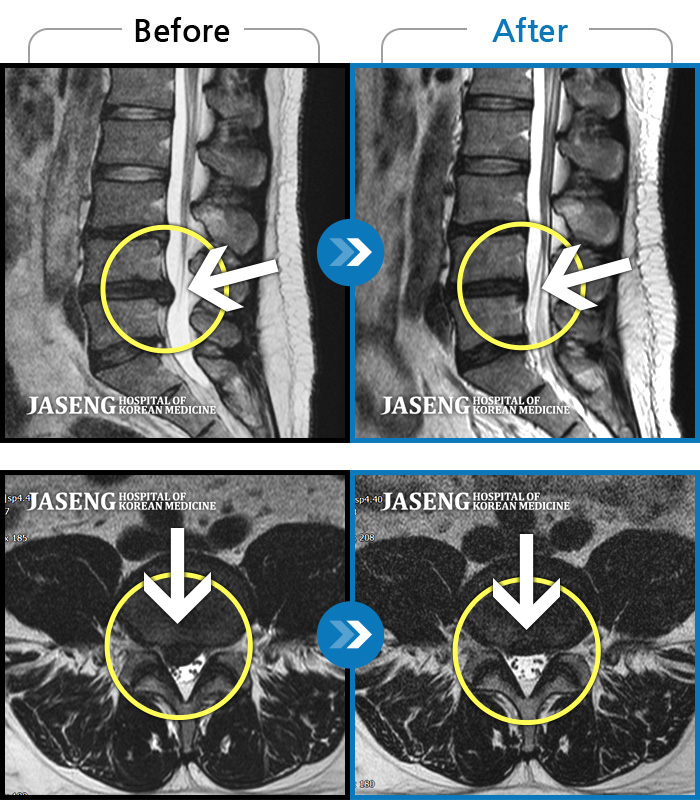

허리디스크

인천 · 강아현 원장

처음 내원시 약 1년 가까이 지속된 허리 통증 및 다리 저림으로 앉아있을 때 통증이 심한 상태였습니다

촬영시기

2020.04.28 ~ 2022.07.30

2022.08.05

조회수 116